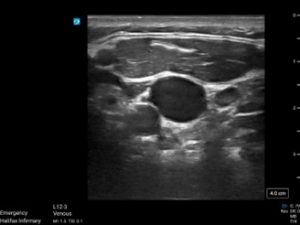

Axillary Vein (Click on images for both videos)

The axillary vein was obtained with the probe in the axilla, with compression then color flow

Axillary vein to the R of the image demonstrated echogenicity, non-compressibility, and no flow, indicating clot presence.